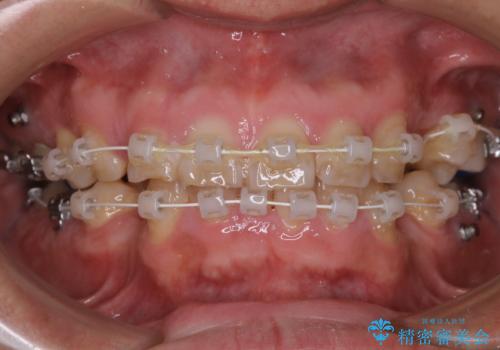

表のワイヤー装置で矯正中にPMTCで綺麗にお掃除

担当医 歯科衛生士